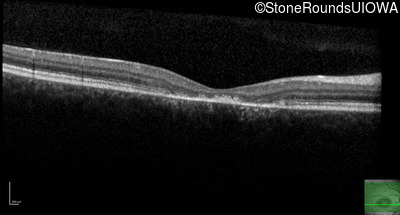

This 16 year old female first had difficulty seeing the blackboard at age 9. Her eye doctor at the time felt at the time that she was "faking it". More recently her eye doctor told her she would be blind by age 20 and suggested she get a seeing eye dog.

| AR Stargardt Disease | ABCA4 | Asp507Tyr GAT>TAT | IVS40+5 G>A | AR |